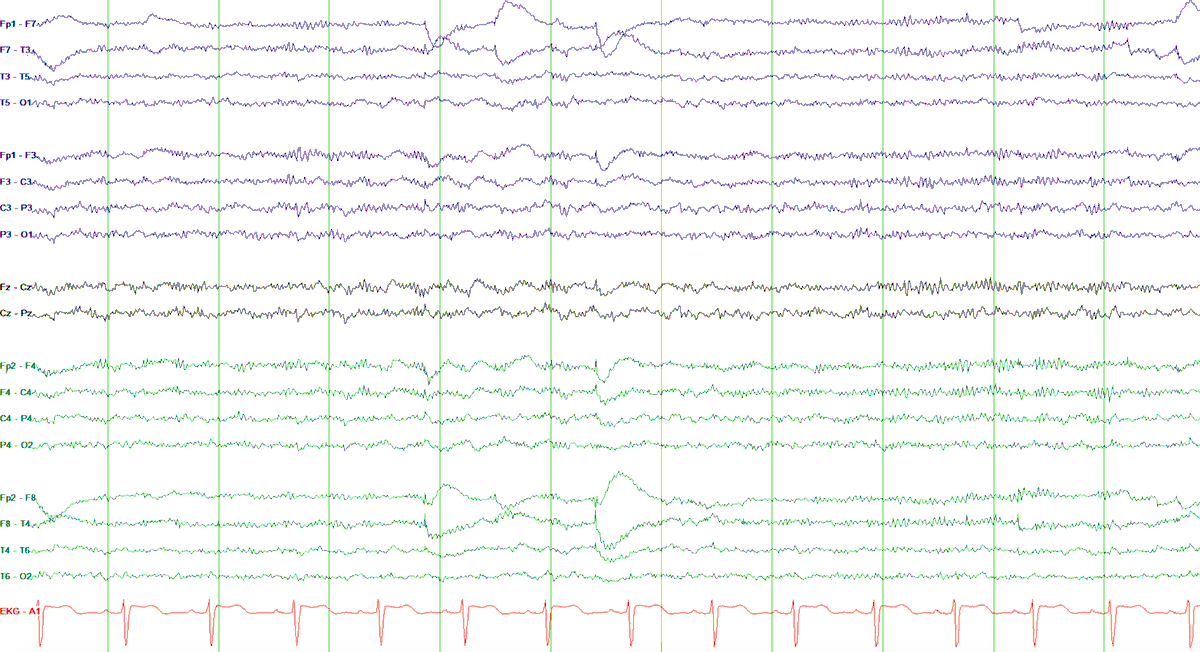

Day #3 of the @childrensatl #SEEg course with Dr Chern discussing SEEG implementation. @SatyaGedelaMD @NeuroSonam @AbedAlwakiMD @DeniseFChen @Raf_Perz